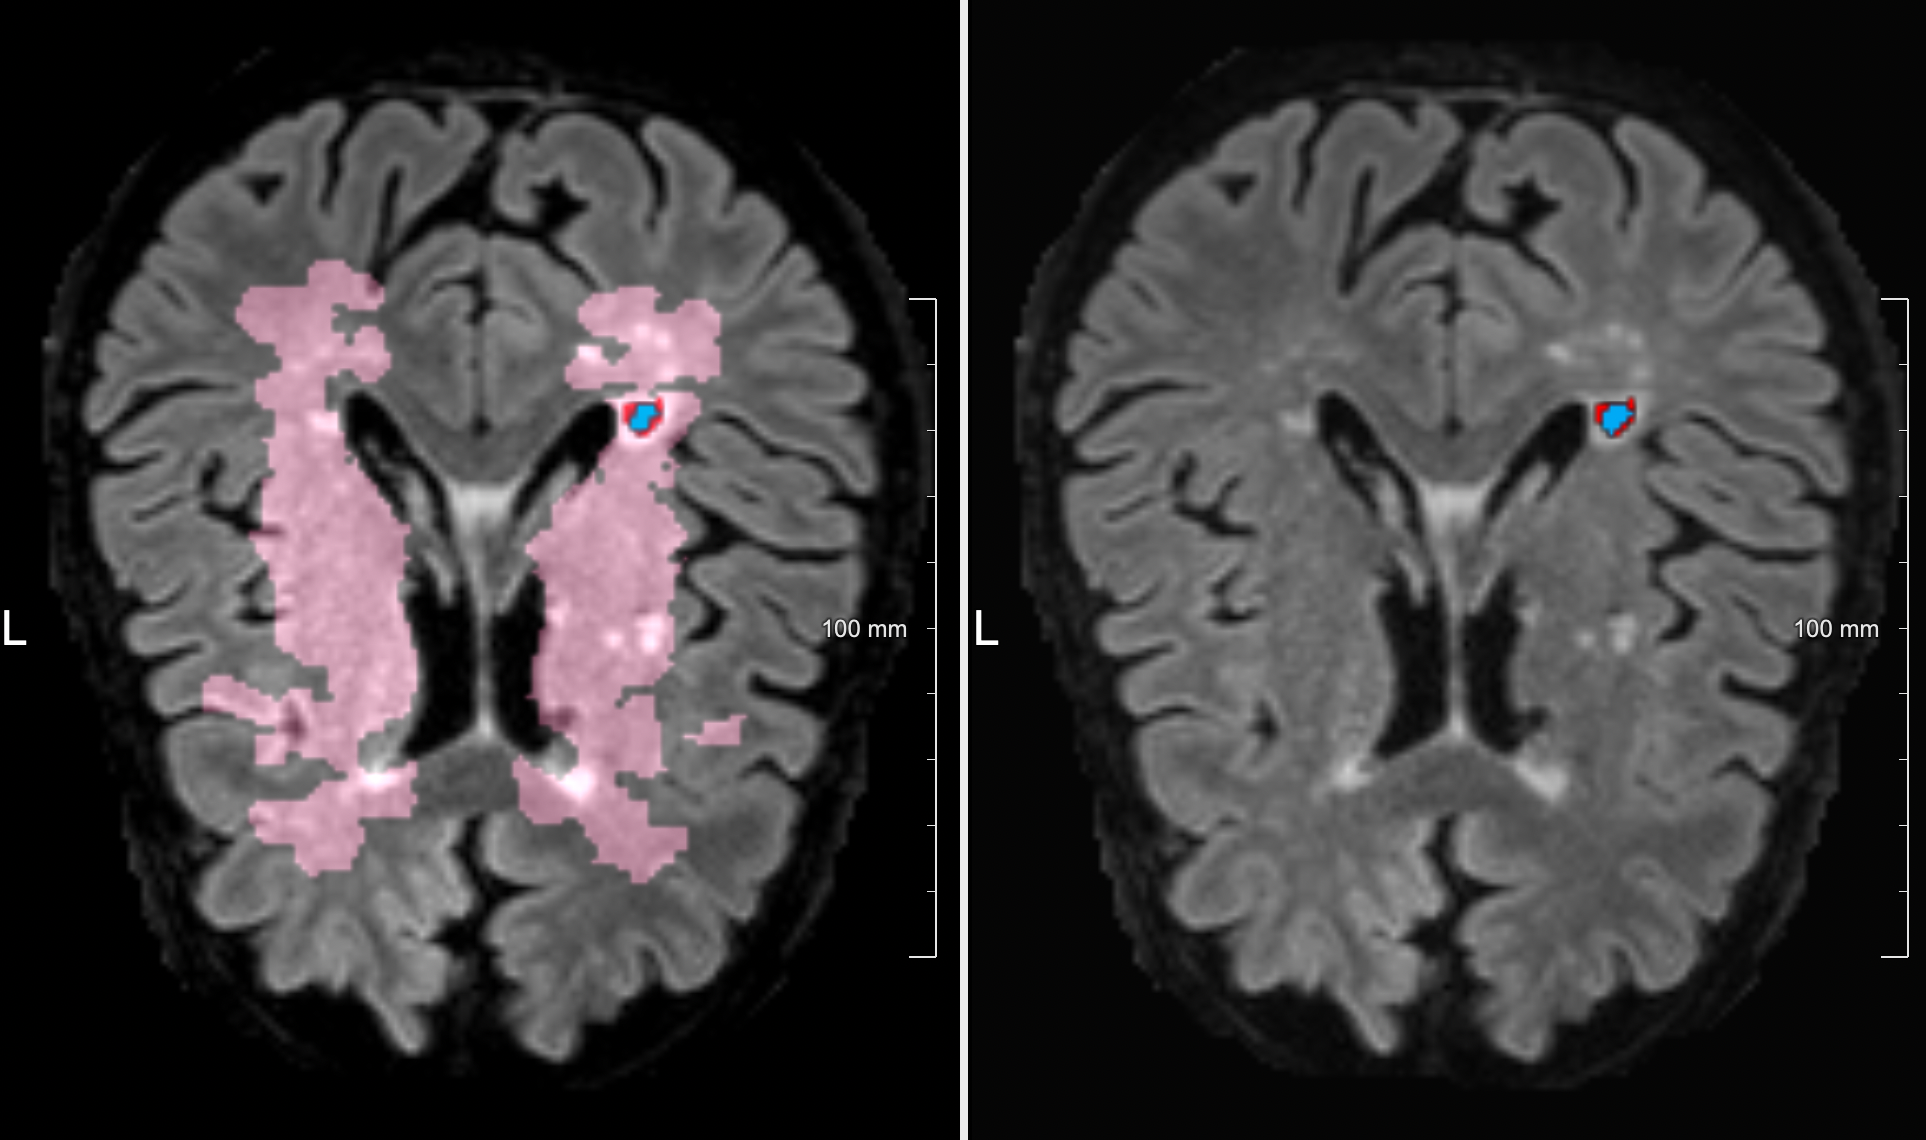

Visual inspection of the results showed that most of the lacunes were correctly detected. An example is shown in Figure 4. However, the predicted binary mask does not precisely match with the ground truth. In some cases, the prediction was a bit smaller compared to its ground truth. A small number of false positive detections remain.

Refer to caption

Figure 4: Example of a correctly detected but slightly under-segmented lacune. Pink is the lacune prevalence map, red is the ground truth segmentation, and blue is the predicted segmentation.